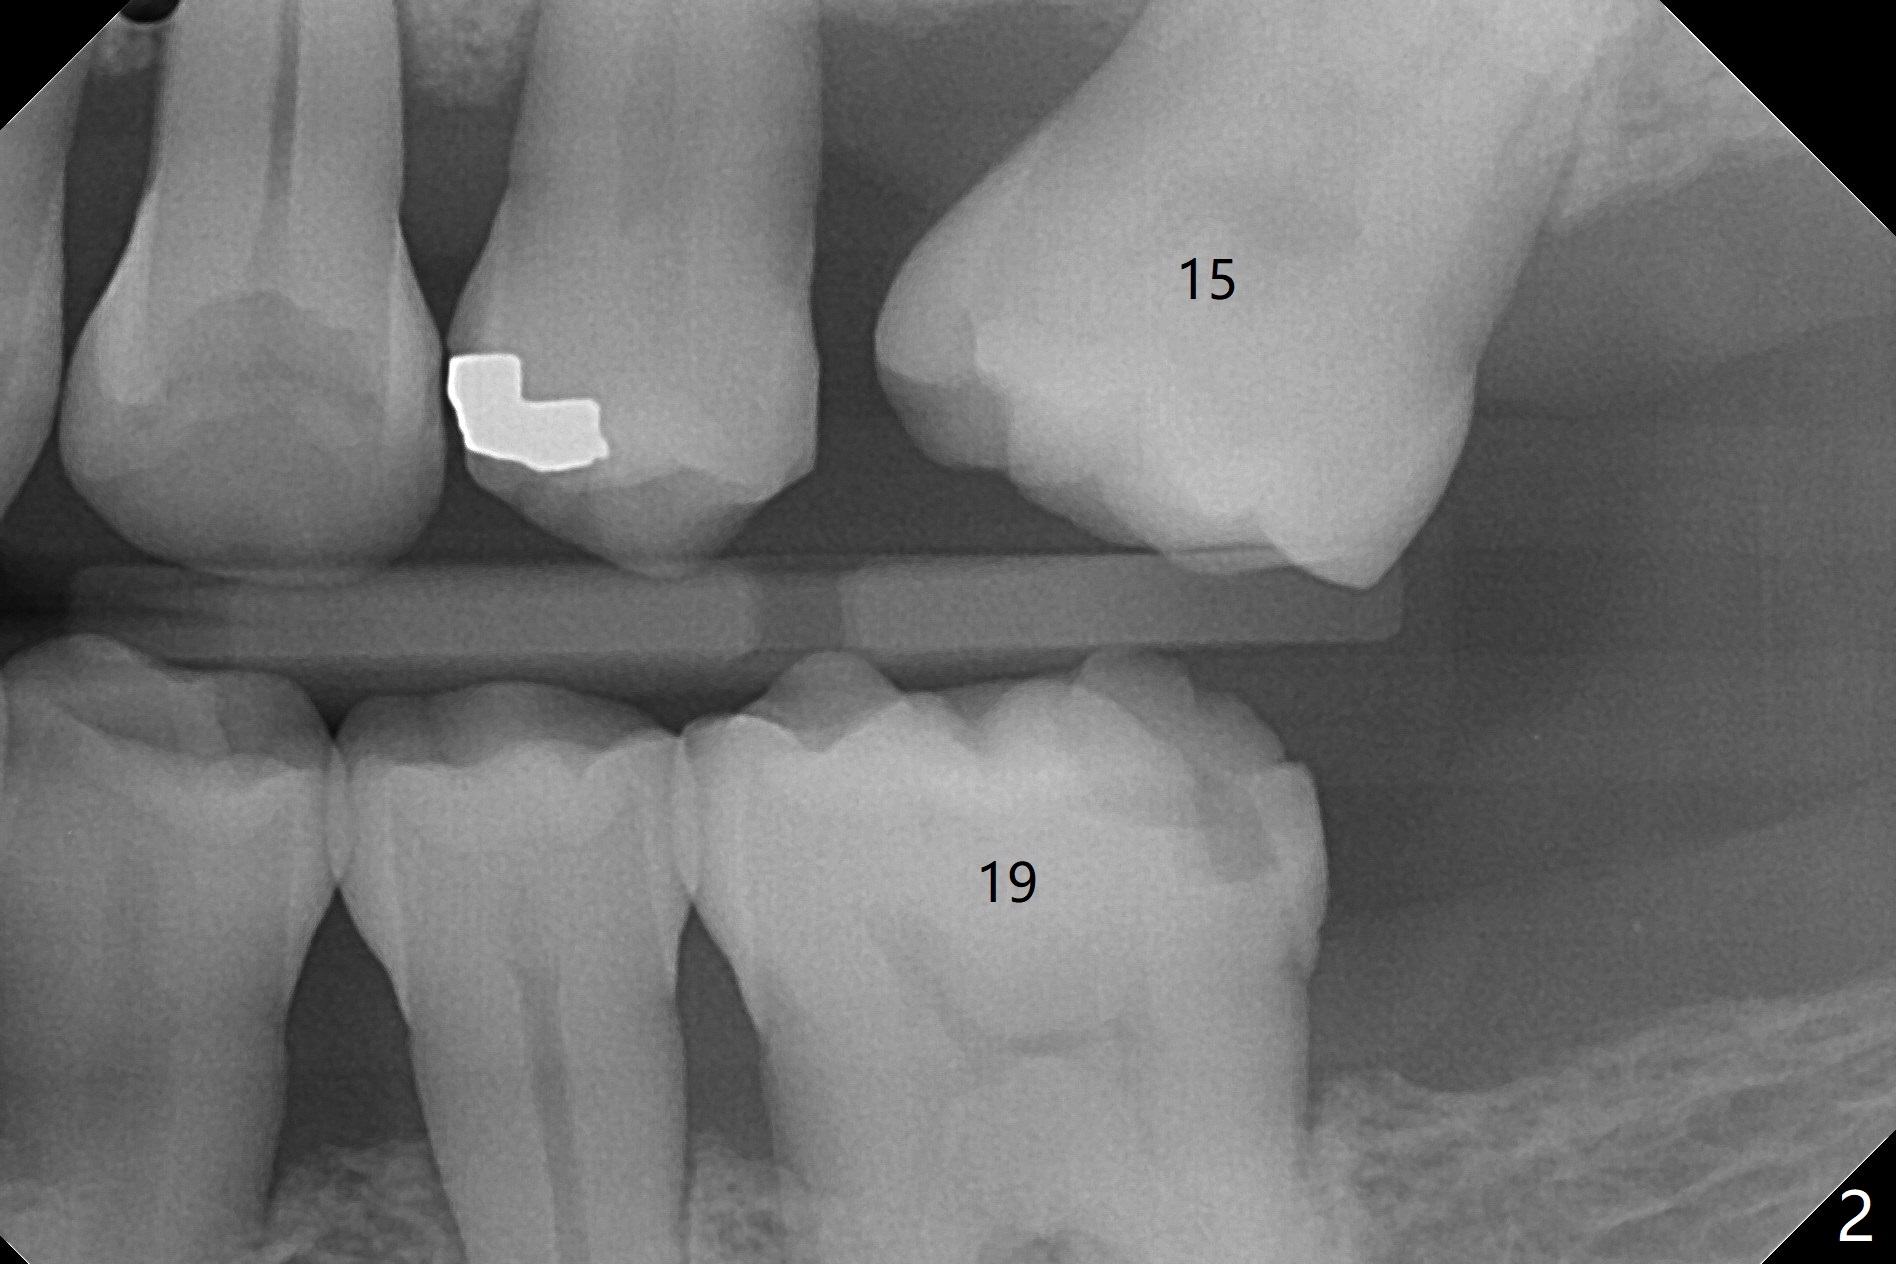

Crown/Implant Ratio

A 53-year-old man has signs of bruxism (Fig.1 diastema *) and root fracture or RCT failure at #4 (Fig.4 (large PARL *)). The RCT failure is related to overload of the affected tooth, which is in turn partially due to infraocclusion of the neighboring implant crown (Fig.1 arrows (implant positioning not ideal)) and partially to due to partial edentulism (Fig.2 missing teeth #14 and 18). For long term, limited ortho will be performed to upright and distalize the tooth #15 (Fig.3 arrow), followed by implants at #14 and 18. For now, the tooth #4 will be extracted (Fig.5), followed by osteotomy in the distal slope of the socket with guide (Fig.6 to get good trajectory). To place a bone-level implant (Fig.7 green), an abutment (blue) with long cuff (pink) is to be used. With poor implant/crown (white) ratio, stress occurs at the junction of the implant/abutment (red arrow), resulting in easy abutment screw loosening. In contrast, stress may be applied to directly to a tissue-level implant (Fig.8 arrow) with less likelihood of abutment screw loosening. The implant/crown ratio improves by approximately 5.5 mm. The roots of the teeth #15 and 16 are so close to each other that interference may occur when the tooth #15 is being uprighted (Fig.9). The empty socket of the tooth #4 is wide buccopalatal (Fig.10); the buccal plate is resorbed coronally (Fig.10 <) so that a 4.5 or 5 mm diameter implant should be placed palatal (Fig.11). Use sticky bone to repair the buccal plate defect and PRF membrane or plug for sinus lift. Following #15 uprighting and distalization, a 5x10 mm implant will be placed at #14; the ridge is triangular (Fig.12 <) so that bone trimmer is needed. A 10 mm long implant will be placed at #18 (Fig.14) to avoid perforating to the submandibular fossa (Fig.13 *).